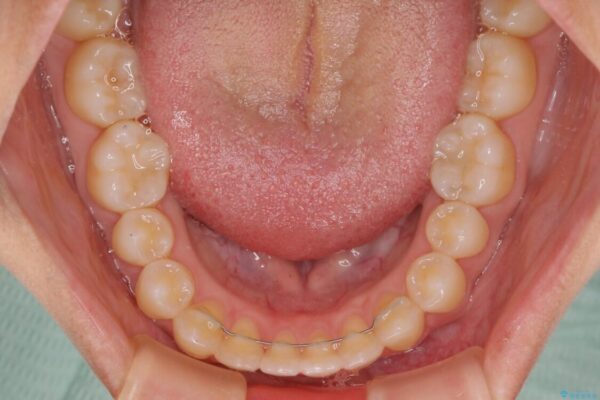

空隙歯列(すきっ歯)は、舌の突出癖をある程度改善できたとしても、後戻りにより隙間が開きやすいと言われています。

裏側から細いワイヤーで保定するとともに、睡眠時のマウスピース装着を徹底していただくことで、後戻りを最小限にとどめます。

治療後

• 隙間だらけの歯列 インビザラインで改善 治療後画像